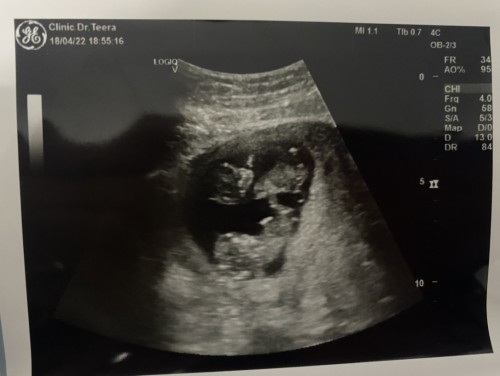

ตรวจดาวซินโดรม ครรภ์แฝด

ครั้งแรกตรวจตอน 5 สัปดาห์ เจอถุงตั้งครรภ์ถุงเดียว ตอนนี้ 11 สัปดาห์ มาแพ็คคู่เลย แม่อายุ 37 หมอแจ้งว่าครรภ์แฝดโรงพยาบาลรัฐไม่ตรวจให้ ถ้าตรวจเอกต้องตรวจแบบไหน ค่าใช้จ่ายประมาณเท่าไรคะ